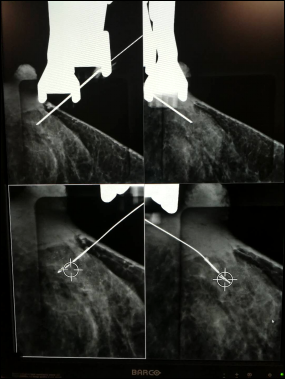

术前1-2小时行钼靶引导下导丝定位。使用美国HOLOGIC钼靶数字乳腺机。将可疑病变置于加压板方形窗口内,取轴位或侧位显示病变部位,由定位仪计算出两个摄影占的预定穿刺点坐标,根据坐标调节穿刺引导架的进针路径及深度,消毒皮肤,以0.5%利多卡因局部麻醉,沿穿刺引导架的进针路径用定位针进行穿刺,进针后按上述方法重复出两个不同角度的定位片,核实针尖已到位,送入内芯,拔出外套管,将定位导丝固定于病变组织内。定位后再行钼靶片检查,核实定位导丝位于病变组织内。即送手术室常规消毒,在导丝进入的皮肤切口,沿导丝向下做圆锥状切割,逐渐增加宽度,连同导丝一并切除;带有导丝的手术标本先送回放射线科摄影,核实病灶是否被完整切除,然后行病理学检查。

图片2.png

图表2:术前乳腺X线示区域分布星形钙化

图片3.png

图表3:成功将定位钩针放置于病灶